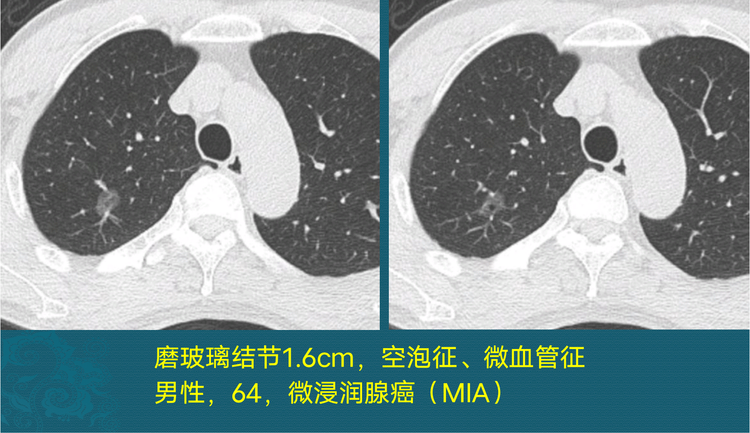

肺磨玻璃结节可以随访多久

右下肺见8mmx9mm磨玻璃密度结节

这位老爷子是咳嗽3天做ct,查出右上肺纯磨玻璃结节,长径1.